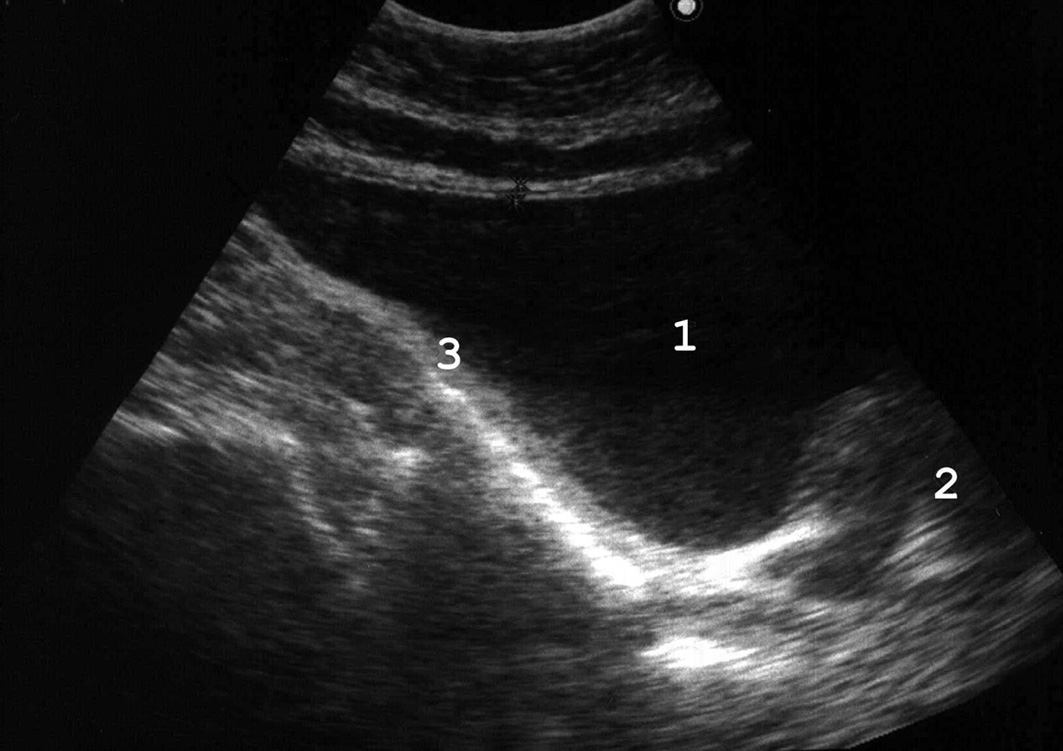

Рис. 5. При хронической задержке мочи вначале развивается гипертрофия мышечной оболочки мочевого пузыря: 1 − мочевой пузырь; 2 − увеличенная простата; 3 − утолщенная стенка мочевого пузыря. (Продольное сканирование, конвексный датчик 5 МГц, “Logiq-500”).

Наиболее часто гипертрофия стенок связана с нарушением оттока мочи вследствие инфравезикальной обструкции. Ее причинами могут быть доброкачественная гиперплазия или рак предстательной железы, функциональный или органический стеноз шейки мочевого пузыря (болезнь Мариона), стриктура уретры. При прогрессировании заболевания и увеличении объема остаточной мочи утолщение мышечных пучков становится неравномерным, внутренняя поверхность мочевого пузыря принимает трабекулярный вид (рис. 6). Длительное существование хронической задержки мочи приводит к дальнейшему истончению стенок пузыря (рис. 7). Объем остаточной мочи может при этом достигать 1 л и более.